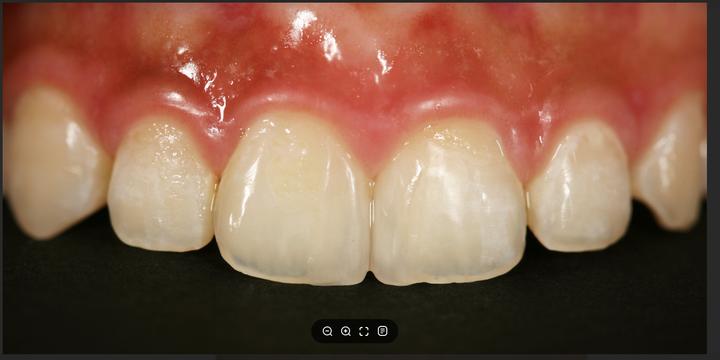

ハル歯科医院は、最先端のインプラント歯科治療に特化したクリニックです。代表のジョー・ハング院長は日本の神奈川歯科大学を卒業し、両国での歯科医師免許を保持。さらに、韓国で専門医資格を取得し、口腔外科など高度な手術経験も豊富です。すべての治療を院長自らが行う専任診療制を採用しており、流暢な日本語で対応可能。「デジタルインプラント」や「無削除ラミネート」などの最新のデジタル歯科治療を、日本の約半額で受けられます。仁川・金浦空港から乗り換えなしで行ける孔徳(コンドッ)駅すぐとアクセスも良好で、旅行者にも便利な立地となっています。